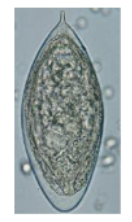

What egg parasite is this?

Schistosoma mansoni

What parasite egg is this?

schistosoma haematobium

Schistosoma japonicum